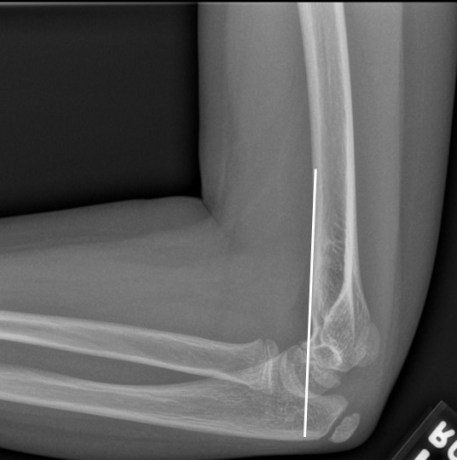

1. Anterior Humeral Line: Drawn along the anterior inferior cortex of the humerus, it should pass through the middle third of the capitellum (a good lateral radiograph is a pre-requisite to apply this rule).

The thinnest part of the bone in the distal humerus is the part where the coronoid and the olecranon fossa come together. In supracondylar fractures, there is some amount of posterior angulation at this point. Thus the anterior humeral line will no longer pass through the middle third of the capitellum. It will either pass through the anterior third or even anterior to that.

The relation of the anterior humeral line with the capitellum is not very accurate at a younger age (some say 2.5 years and others say 5 years). Essentially, the older the child the more reliable is the anterior humeral line.